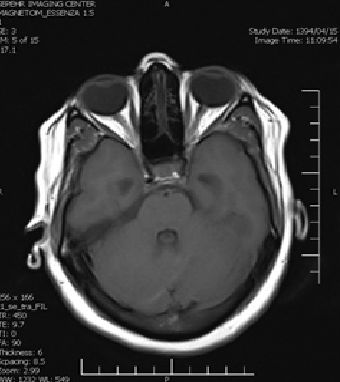

An Occipital Headache as the First Presentation of Multiple Third, Fourth, and Lateral Ventricular Cavernous Malformations: A Case Report and Review of Literature

Background: Cavernous hemangiomas are common benign vascular malformations. Their existence in the intraventricular region is very rare. Case Reports: A 43-year old woman with an occipital headache was admitted to the emergency ward. Brain computed tomography scan showed mild hydrocephalus and multiple intraventricular isodense lesions. Imaging findings, especially of Gradient Resonance Echo imaging, were in favor of multiple intraventricular cavernous malformations. Conclusion: This is a rare presentation of multiple cavernous malformation as occipital headache without needing surgical intervention in this phase. Coexistence of periventricular plaques like Radiologically isolated syndrome of Multiple sclerosis is another unique aspect in this report. [GMJ.2017;6(1):61-65]